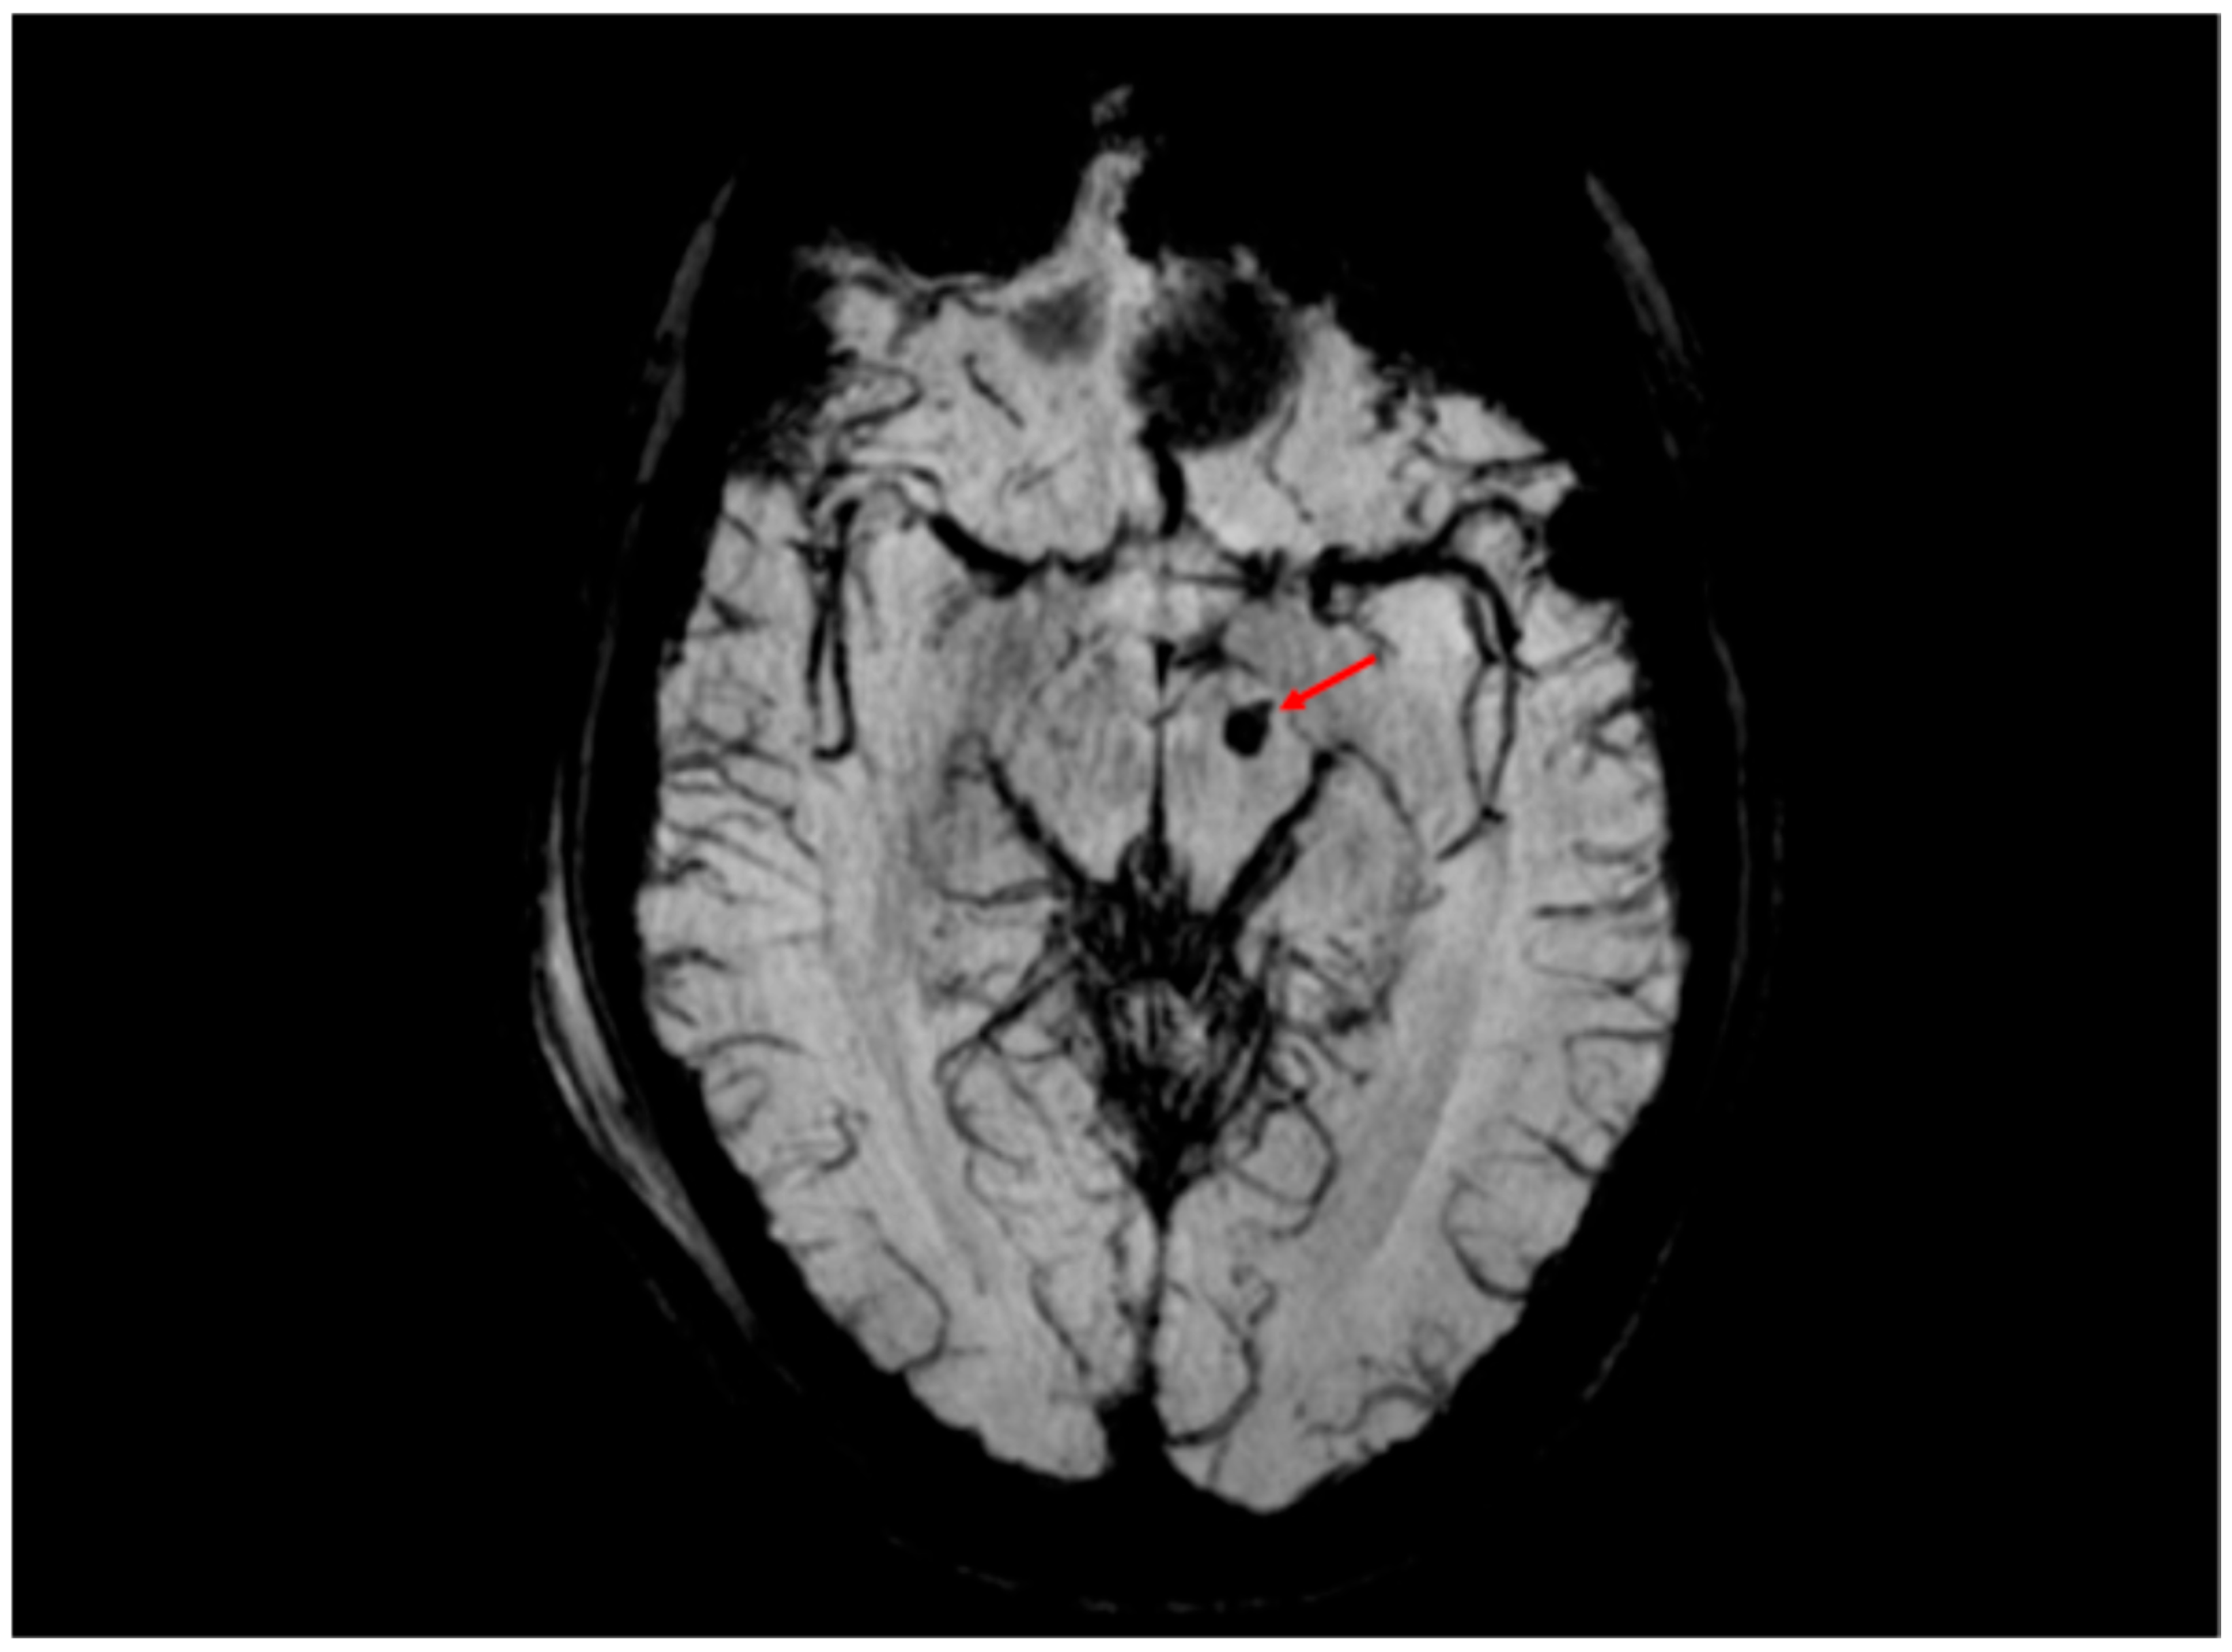

5.3.1. Radiological Findings in Adult DAI

- Abu Hamdeh, S.; Marklund, N.; Lannsjö, M.; Howells, T.; Raininko, R.; Wikström, J.; Enblad, P. Extended anatomical grading in diffuse axonal injury using MRI: Hemorrhagic lesions in the substantia nigra and mesencephalic tegmentum indicate poor long-term outcome. J. Neurotrauma 2017, 34, 341–352. [Google Scholar] [CrossRef]

- Moen, K.G.; Flusund, A.M.H.; Moe, H.K.; Andelic, N.; Skandsen, T.; Håberg, A.; Kvistad, K.A.; Olsen, Ø.; Saksvoll, E.H.; Abel-Grüner, S.; et al. The prognostic importance of traumatic axonal injury on early MRI: The Trondheim TAI-MRI grading and quantitative models. Eur. Radiol. 2024, 34, 8015–8029. [Google Scholar] [CrossRef]